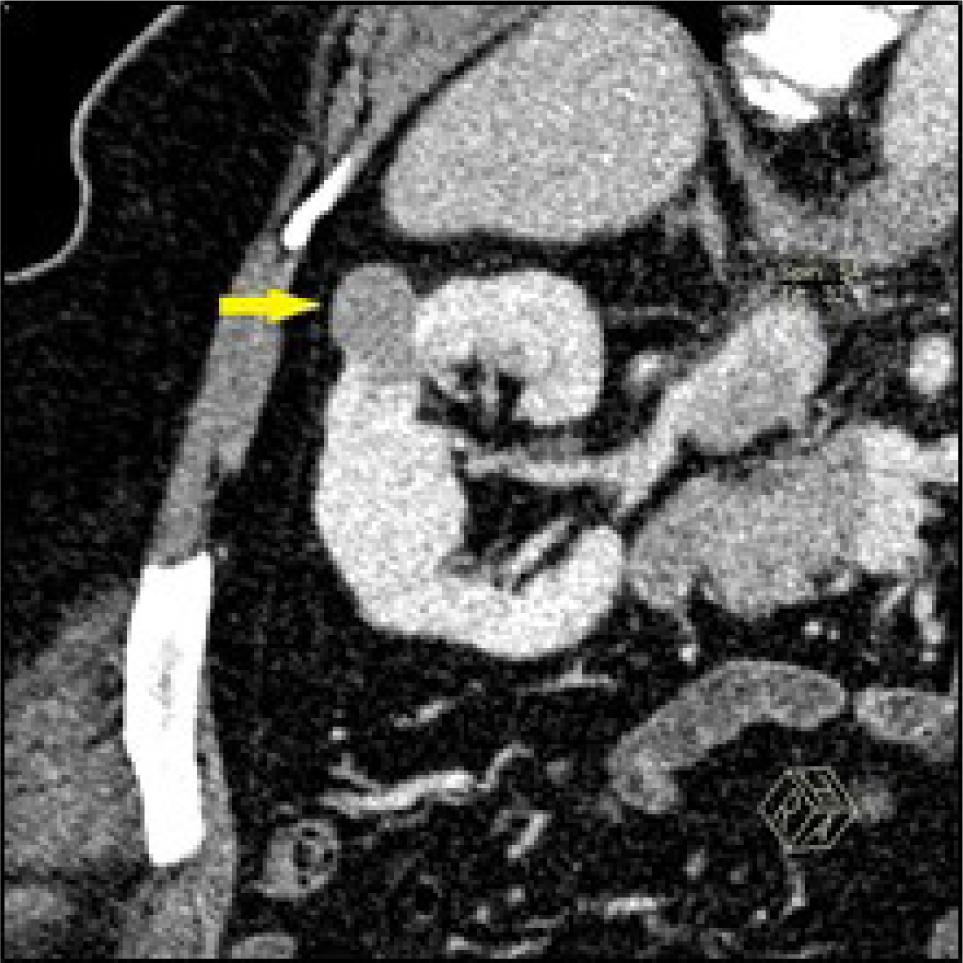

Figure 3: Coronal oblique reformatted CT image of the right kidney in nephrographic phase in a 36-year-old female, showing a 31 mm solid exophytic mass lesion (Arrow) with evident angular interface sign. The mass was enucleated and confirmed lipid-poor angiomyolipoma.